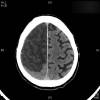

AVC amplio de territorio de A. cerebral media

Hematoma subdural por caída.

Atrofia cortico-subcortical de predominio frontotemporal.